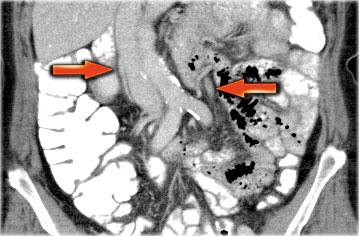

Một phương pháp hữu ích để xác định buồng trứng là theo dõi tĩnh mạch buồng trứng theo hướng đuôi.

Hãy cuộn qua các hình ảnh CT và theo dõi tĩnh mạch buồng trứng phải từ vị trí đổ vào tĩnh mạch chủ dưới, và tĩnh mạch buồng trứng trái từ vị trí đổ vào tĩnh mạch thận trái, cho đến khi xác định được buồng trứng.